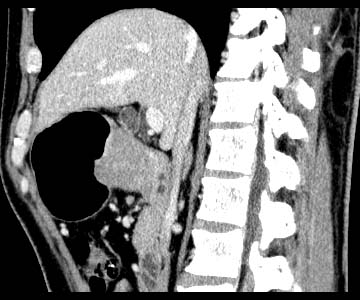

Gastric cancer / Borr.II

Sagittal MPR

Data acquired & processed by R. Kato M.D.